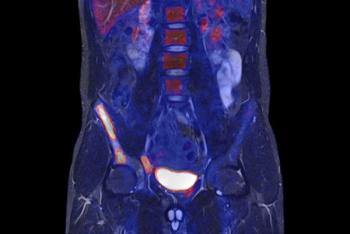

PET/MR has a promising future, but radiology practices will need deep pockets to implement the systems.

PET/MR in action.